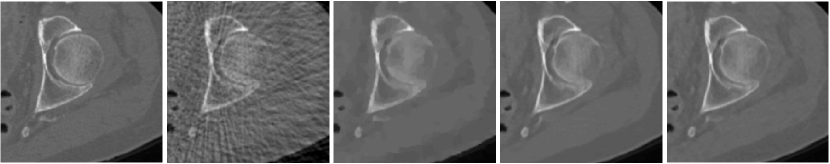

Fig. 2 (a) illustrates the reconstructions of a test image for case when measurement is noiseless. FBP is dominated by line artifacts, while TV satisfactorily removes these but blurs the fine structures. FBPConv and RPGD, on the other hand, are able to reconstruct these details. The zoomed version shows that RPGD is able to reconstruct the fine details better than the others. This observation remains the same when the measurement quality degrades. Fig. 2 (b) shows the reconstructions for 45-dB and 40-dB noise levels. In these scenarios, RPGD40 is significantly better than both FBPconv40 and TV.